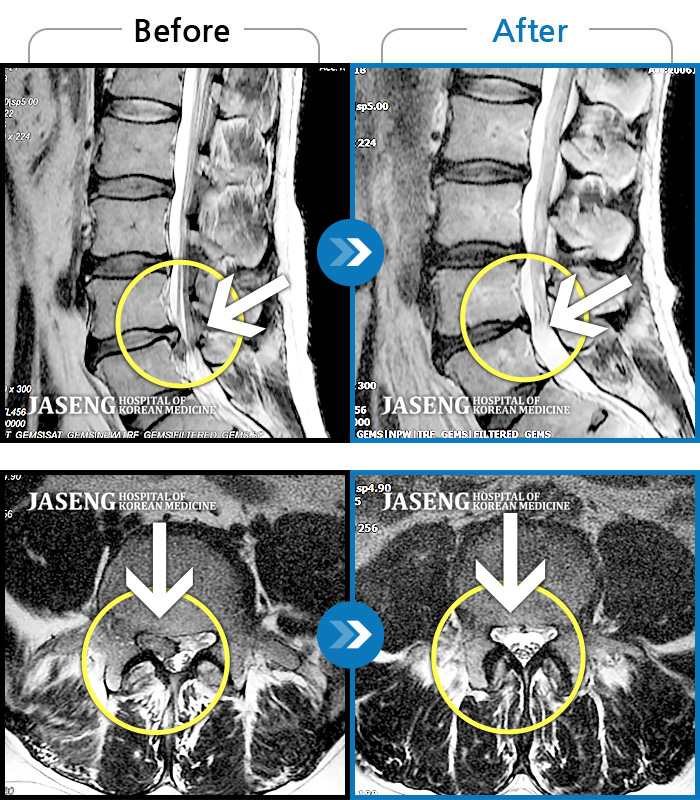

Before

After

환자에게 사전 동의를 받아 동일 조건에서 촬영되었습니다.

개인에 따라 치료 후 부작용이 발생할 수 있으니 의료진과 상담 후 치료를 진행하시기 바랍니다.

허리 및 양쪽 골반에 심한통증으로 일주일간 거동이 불가능 했으며 우측 하지로 방사통이 심한 상태

서 있을때 아프고, 아침에 자고 일어나면 골반이 욱신욱신하게 아프고 다리가 아파요. 발 디딜때 마다 심하네요.